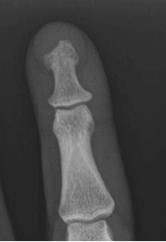

En la Rx simple hay pocos signos específicos. Es característica la reabsorción de los penachos distales de las falanges, la reacción perióstica algodonosa y el afilamiento en la parte distal de las falanges, originando el signo de lápiz en copa. (1,2). (Fig 54 B).

Fig 54 B. Artropatía por psoriasis.

Rx AP. Reabsorción de la falange distal.